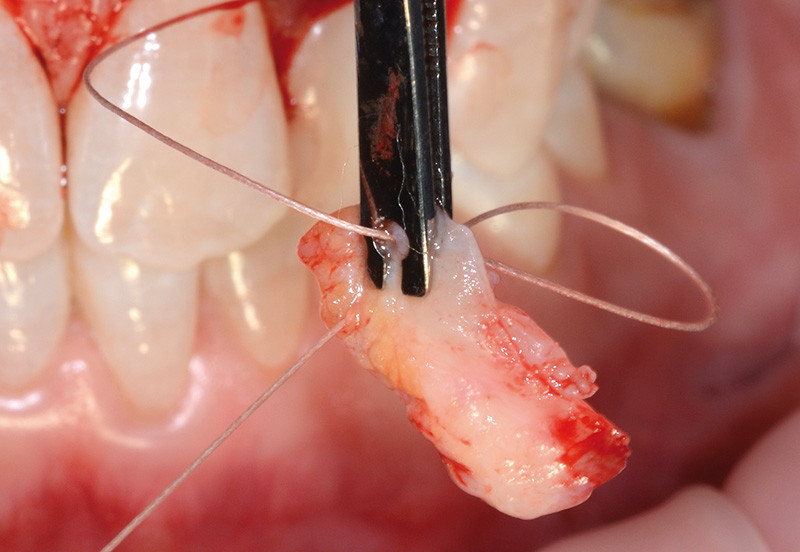

bibli/3.1.11.jpgUn second fil est passé dans le greffon à son autre extrémité.

bibli/2.3.jpgDeux fils sont préalablement montés sur le greffon dans son sens horizontal.

bibli/2.3.jpgDeux fils sont préalablement montés sur le greffon dans son sens horizontal.